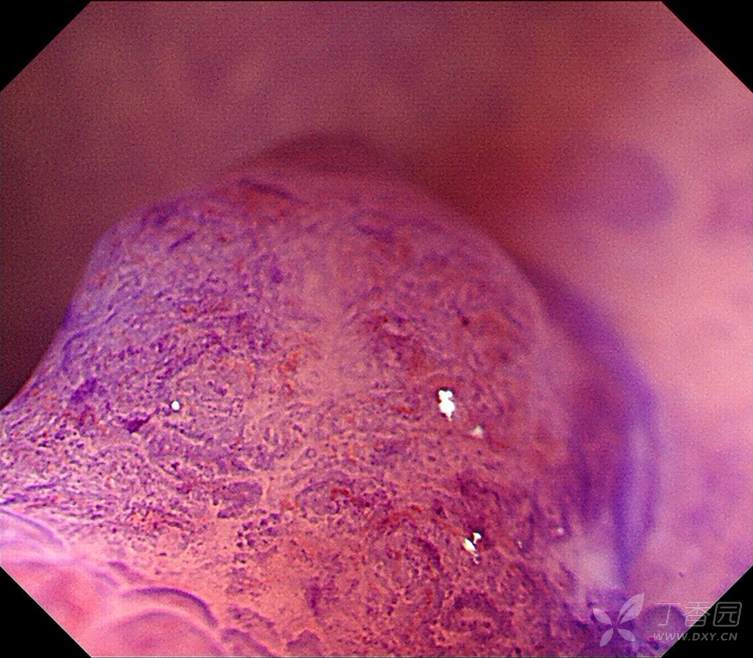

专注早癌诊断,从整体形态到微观表面,详细的判断:JNET、Pit pattern、浸润深度?

这是在跟老师发现的一例病人,在发现病人之后,通过不同的方法,比如NBI、放大、化学染色,对这个病变通过不同的角度,从宏观到微观细致的观察,详细的分析,以便于大家能够更好的理解:

一、pit pattern 分型的实际具体的形态是什么样子的?

二、JNET分型的特点和细微差别又是什么?

三、不同形态的病变,不同的分型的相应形态下对应的病理状态是什么?